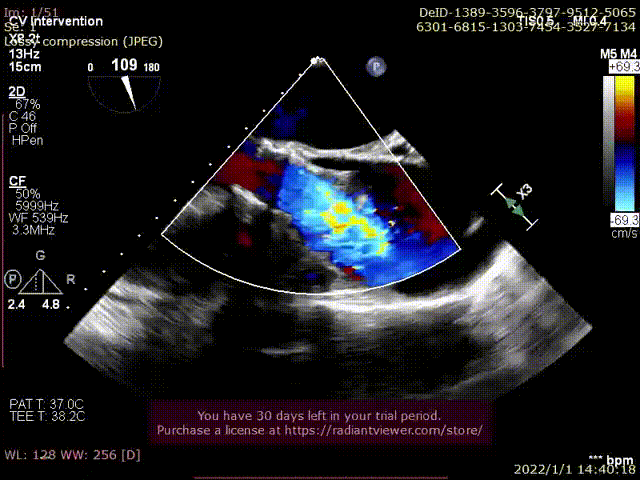

入院超声评估LVEF值仅为39%,TNT 197ng/ml,NT-proBNP 13231pg/L,CREA 67 μmlo/L,BP 86/42 mmHg,STS score 7.325%。超声诊断为瓣膜性心脏病主动脉瓣狭窄(重度),主动脉瓣反流(中度),二尖瓣关闭不全(中度)。左房扩大;左室壁增厚;左室整体运动幅度普遍降低。左室收缩功能减低。微量心包积液。此次患者急诊入院即发生急性左心衰,予IABP维持下生命体征尚平稳,经结构性心脏病团队评估患者无法耐受传统外科开胸手术,遂拟行TAVR手术治疗。

术后超声评估: